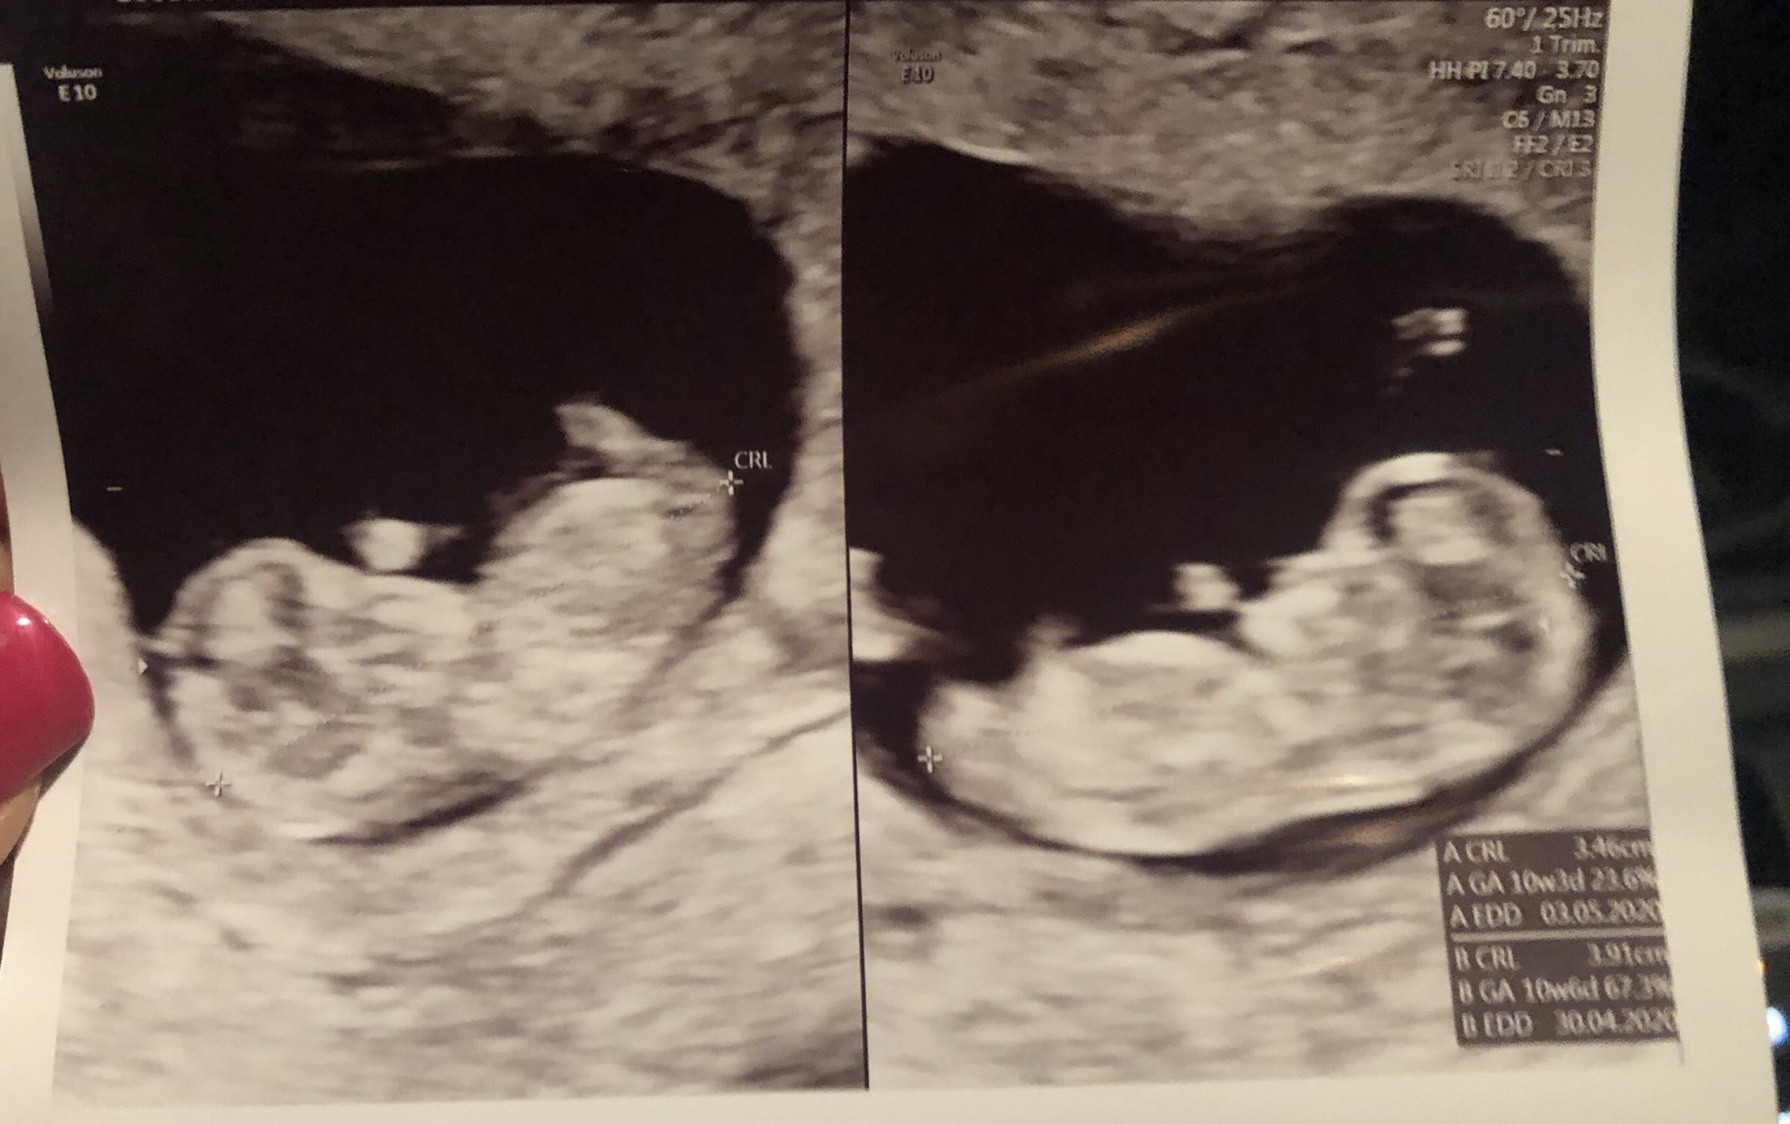

U nas wszystko w porządku. Serducha biją! [emoji173]️

10t6d

Kuleczki rosną i szaleją w brzuszku [emoji7]

Niesamowite uczucie patrzeć jak się wyginają i machają rączkami [emoji4]

Wstawiam zdjęcie tu i na wątek Wizytowy.